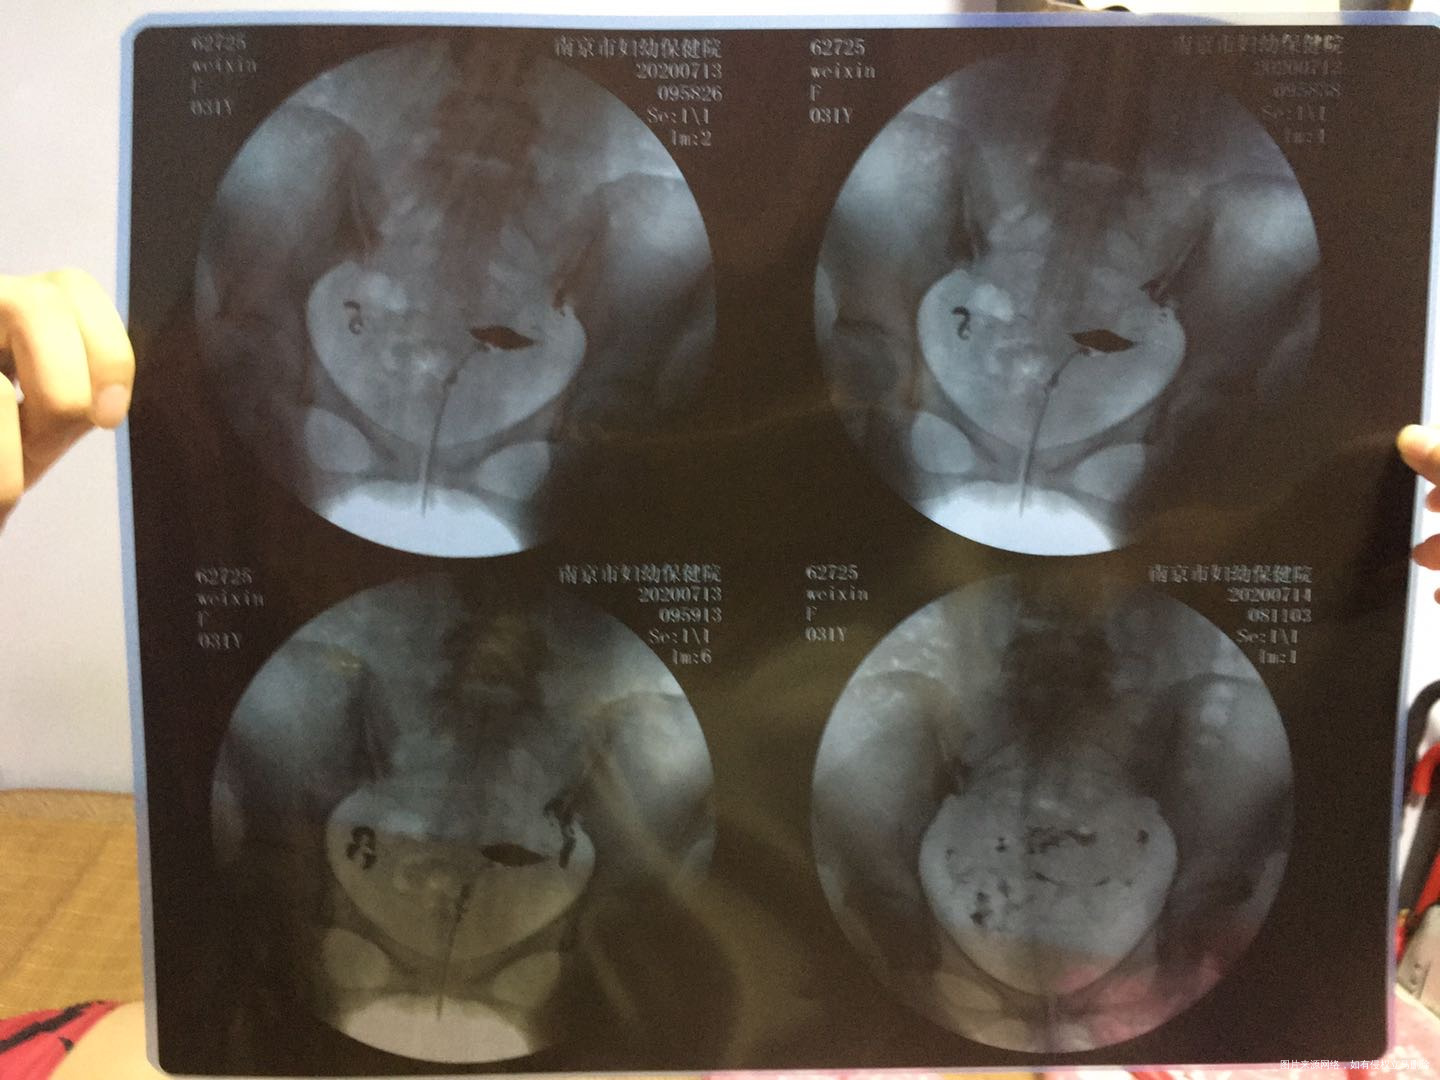

2)做了输卵管造影,显示两侧轻度粘连。祥见下图。

请问我目前备孕一年未怀孕的原因可能是哪个方面呢?黄体激素和雌二醇偏高是什么原因呢?平时需要注意什么?输卵管轻度粘连从片子看很严重吗?必须需要手术治疗吗? 是宫腔镜还是腹腔镜还是导丝介入?远端粘连得话导丝介入效果好嘛?我有盆腔粘连吗?这个需要怎么治疗呢?没有手术史,请问是什么原因造成粘连呢?